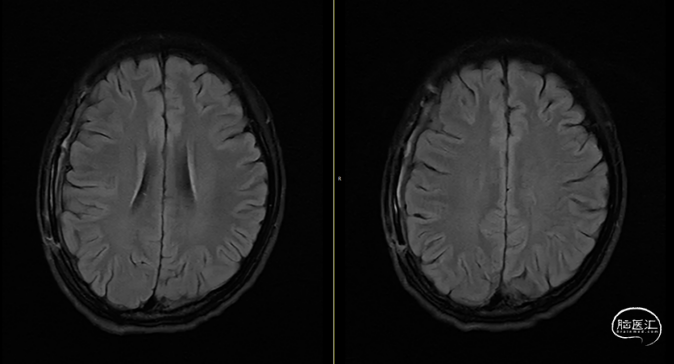

第2次术后12天,仍有间断头痛,刀口愈合可,复查颅脑MRI(如上图):右侧额顶颞部软组织稍增厚,右侧额顶部颅板下见条片状长T1、长T2信号,T2FLAIR呈稍高信号,边界清,DWI(b=1000)呈混杂高信号,相应ADC呈混杂高信号影,加用美罗培南联合万古霉素抗炎治疗。